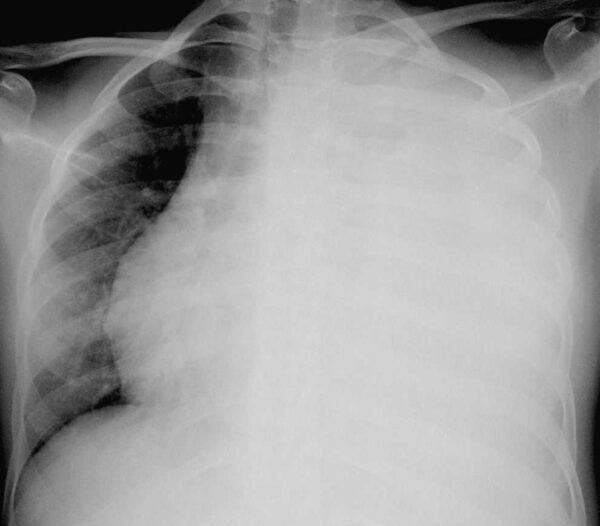

Debe haber cerca de 75 a 100 ml de líquido pleural en el surco costofrénico posterior para ser visibles en la imagen lateral y 175 a 200 ml en el surco costofrénico lateral para delinearse en la imagen frontal de una radiografía de tórax en posición supina. El líquido pleural puede quedar atrapado (tabicado) por adherencias pleurales y formar en consecuencia acumulaciones poco comunes a lo largo de la pared lateral del tórax o dentro de cisuras pulmonares.

El derrame pleural masivo que causa opacificación de la totalidad de un hemitórax se debe con mayor frecuencia a cáncer, pero puede observarse en la tuberculosis y otras enfermedades.